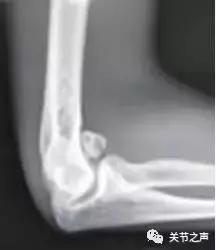

除了肩关节,髋、膝、踝、肘、腕几乎全身各个关节都有可能长珍珠。